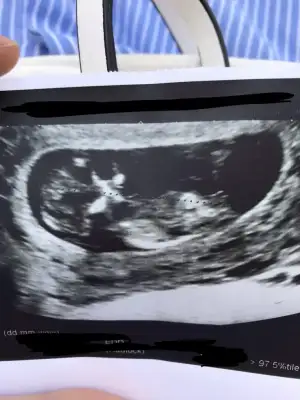

Cinsiyeti hakkında tahminde bulunabilir misiniz kızlar ?

Eklentiler

• F83C4C07-A629-4948-AC12-2E6402178F4F.webp

F83C4C07-A629-4948-AC12-2E6402178F4F.webp

36,2 KB · Görüntüleme: 27

Bencede erkek bebiş 🙏🏽

Sanırım cinsiyeti erkek çünkü direk yukarı doğru bi çıkıntı vardı net şekilde :D doktor bile erkek büyük ihtimal dedi,

Bakalım 3 hafta sonra tatil öncesi kontrole gideceğim o zaman net belli olur :))